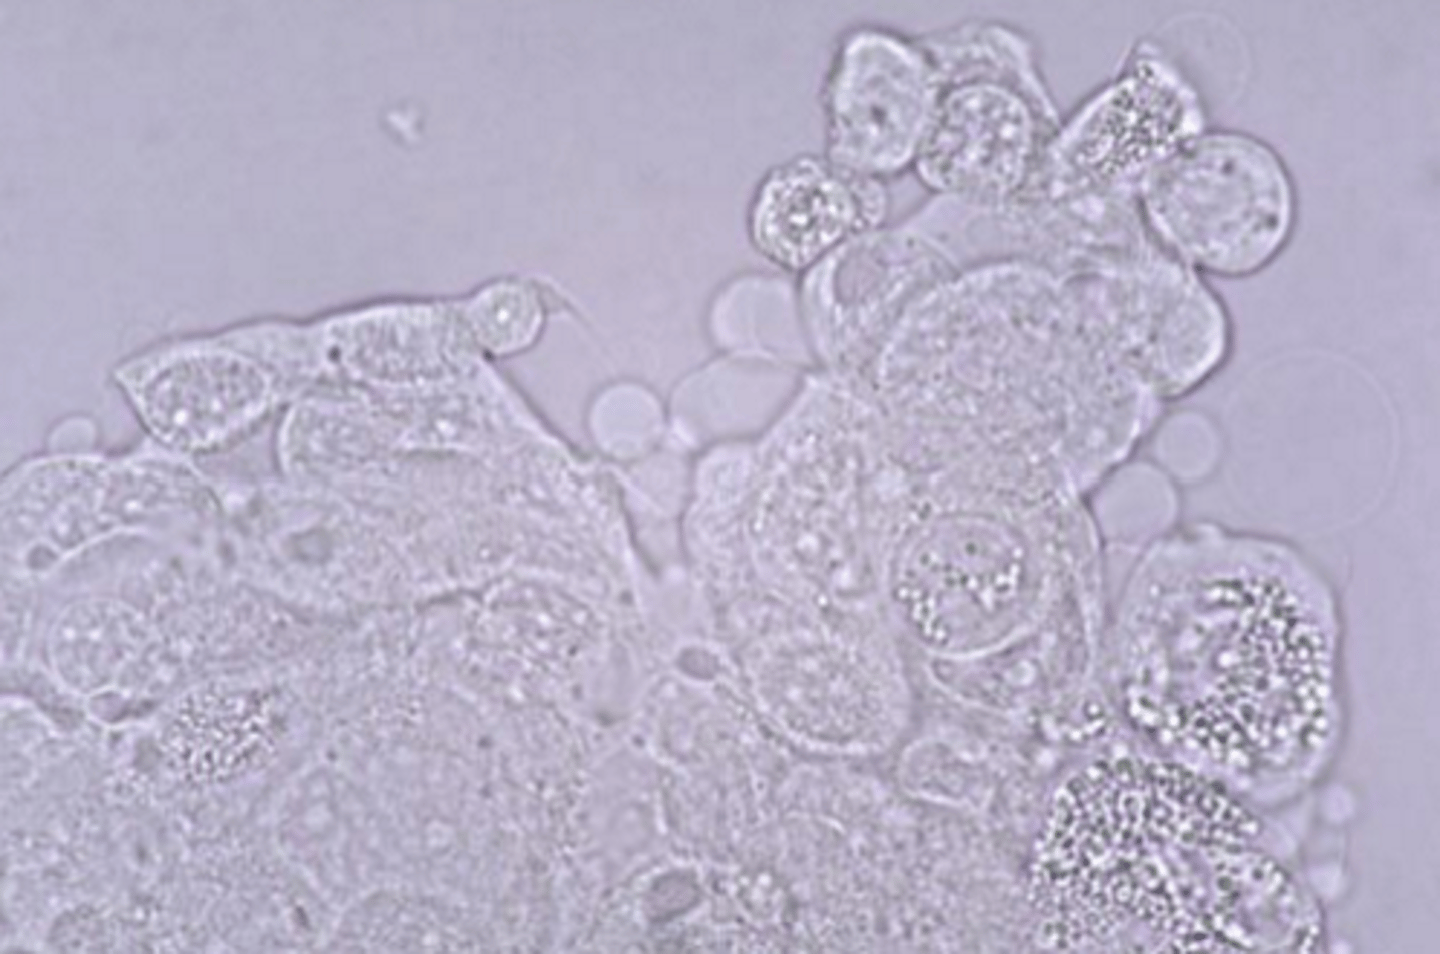

transitional cell carcinoma (TCC)

- malignant neoplasia of epithelial cells

urine

transitional cell carcinoma

urine